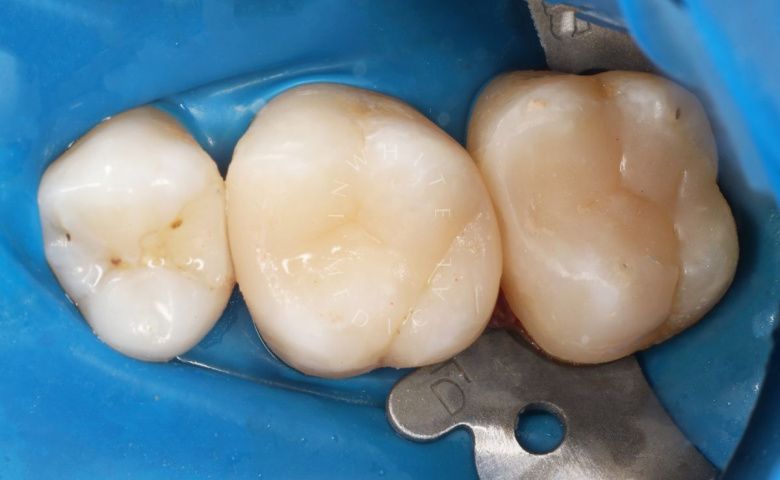

Художественная реставрация формы зубов

До После